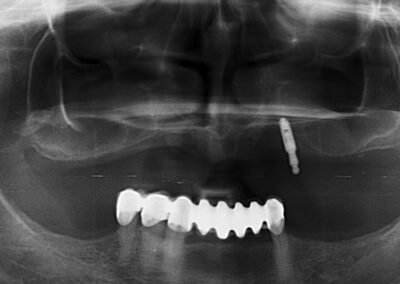

Pacijentu je nedostajao prvi molar u bočnoj regiji. Ovaj zub je posebno značajan i njegov nedostatak narušava kontinuitet celog zubnog luka. Imajući u vidu da su susedni zubi bili zdravi, kao idealno rešenje sa pacijentom je dogovorena ugradnja implanta i protetska nadoknada na implantu.

Na rendgen snimcima prikazana je donja vilica pre ugradnje implanta i donja vilica nakon perioda srastanja (oseointegracije) implanta sa koštanim tkivom.